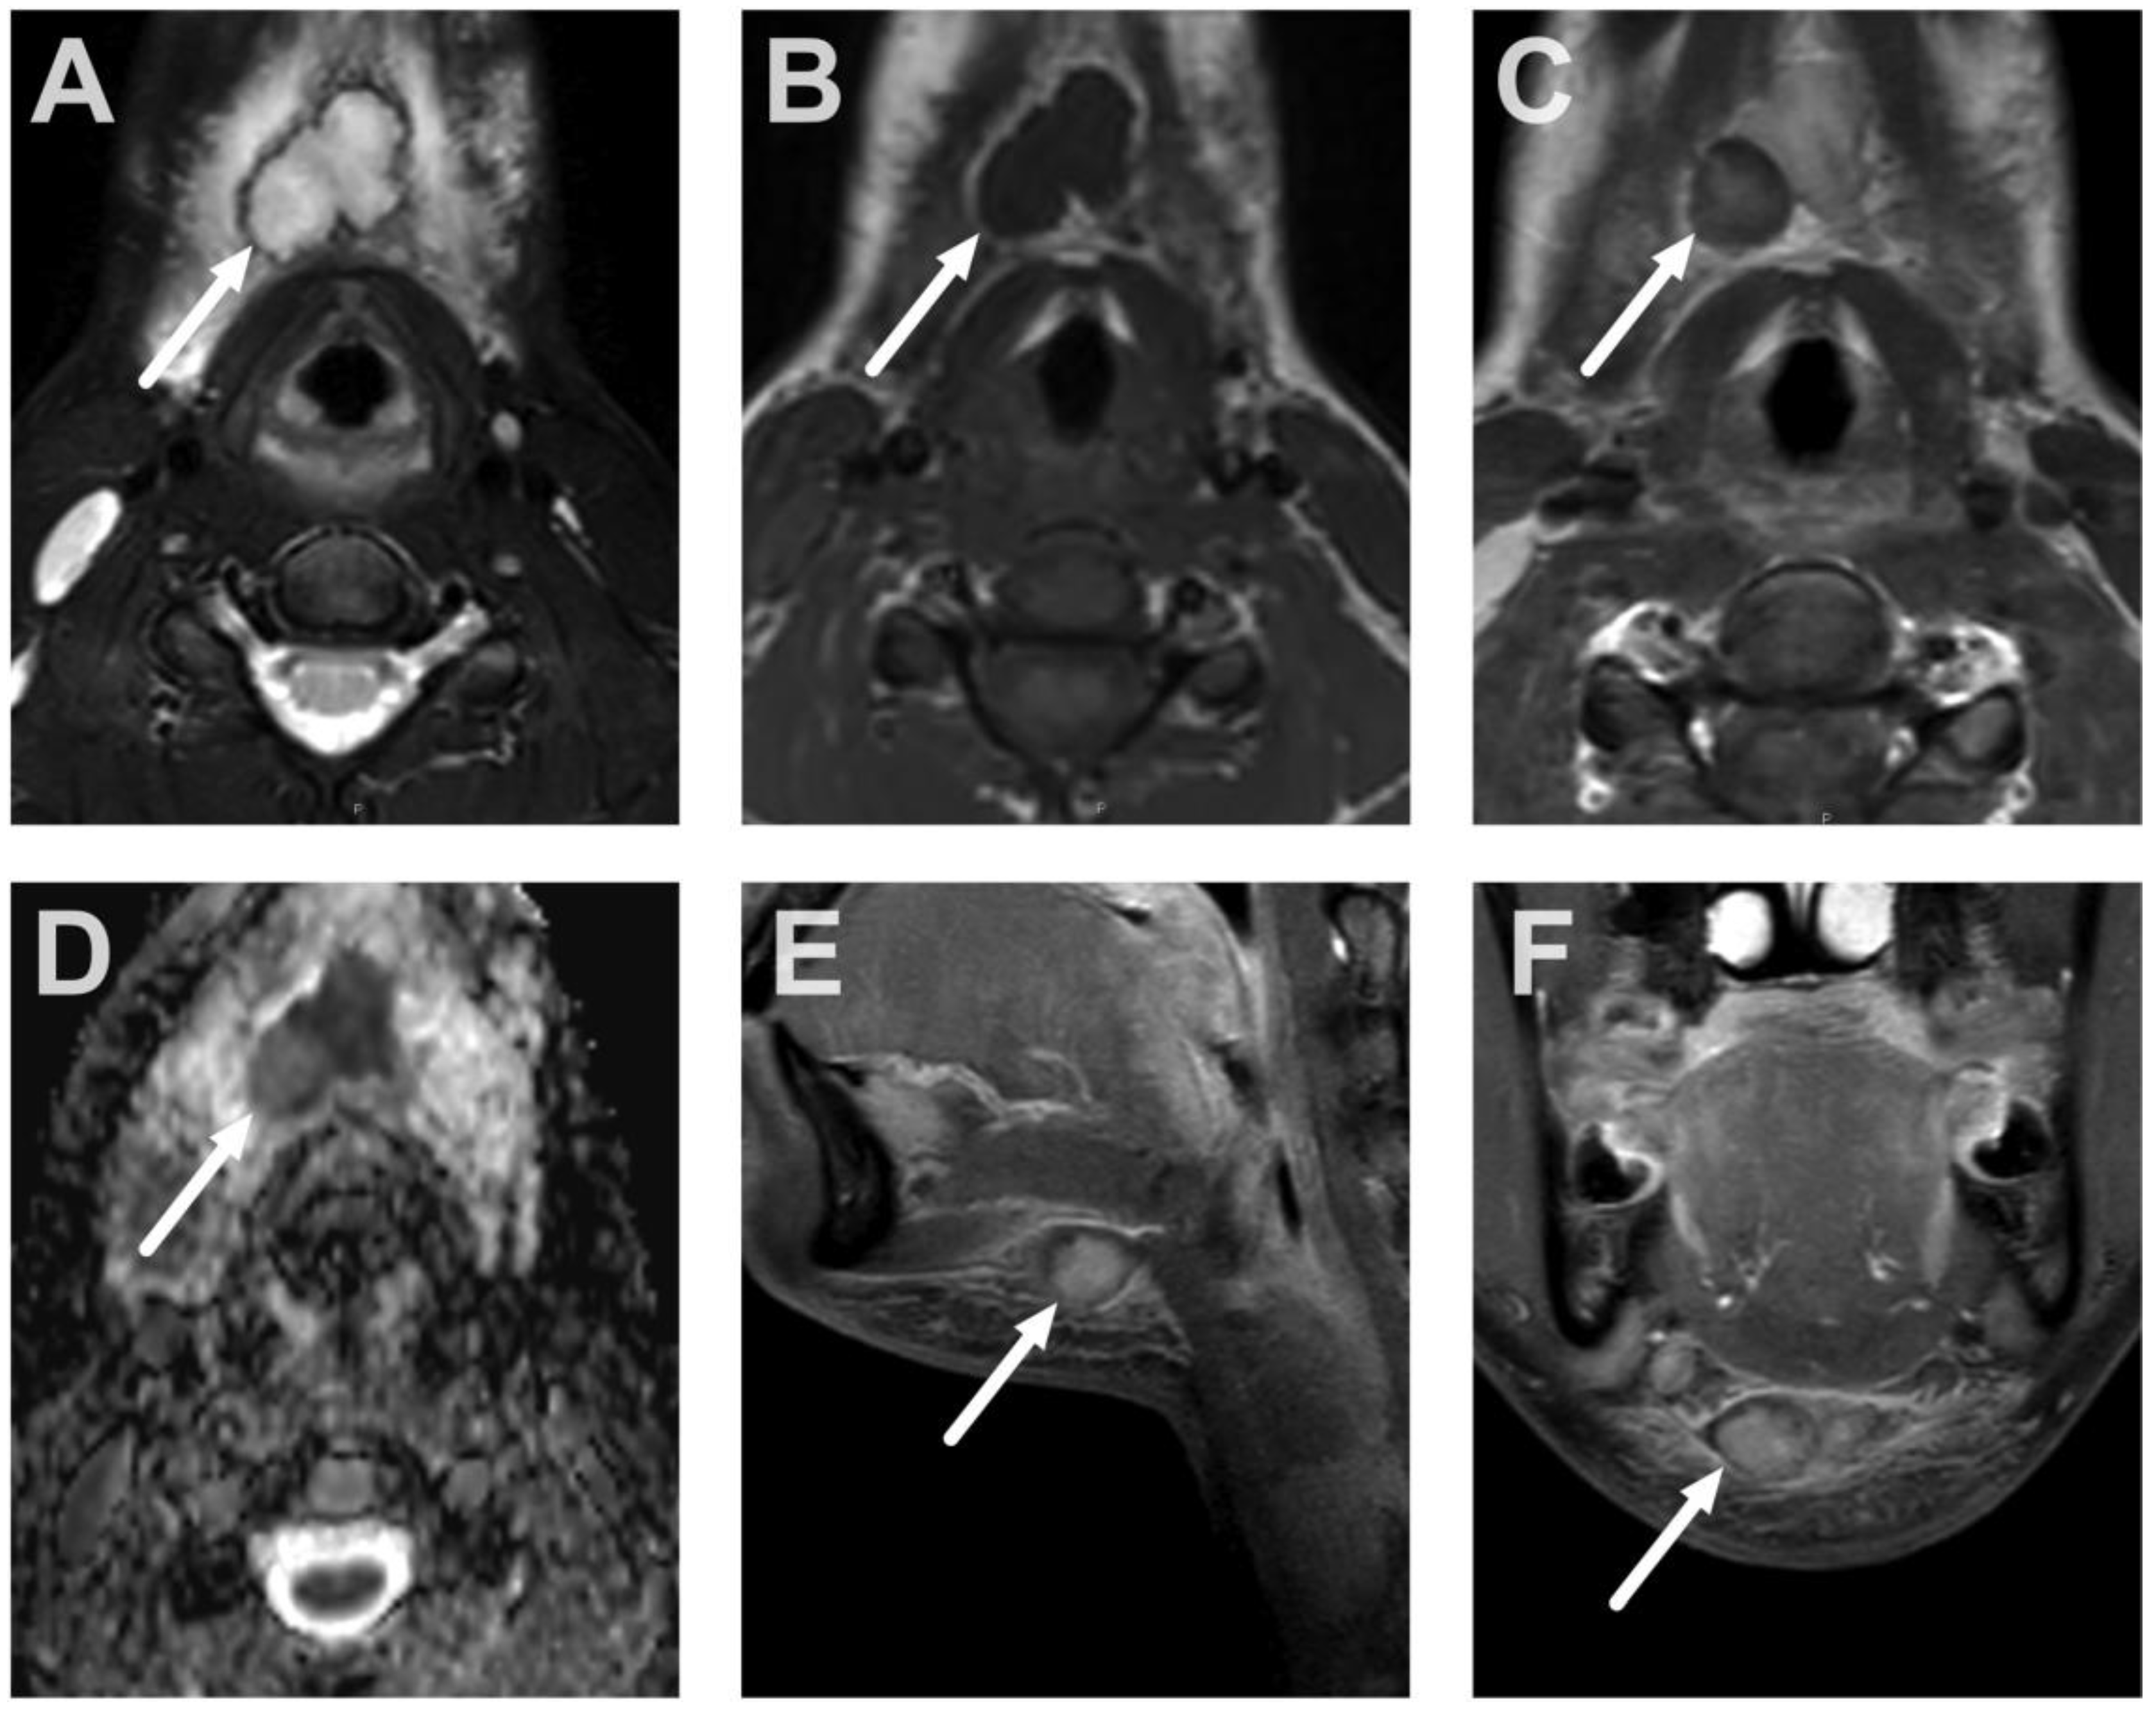

4.2. Retropharyngeal Abscesses and Suppurative Lymphadenitis

5.1. Lymphadenitis with Purulence vs. Necrosis